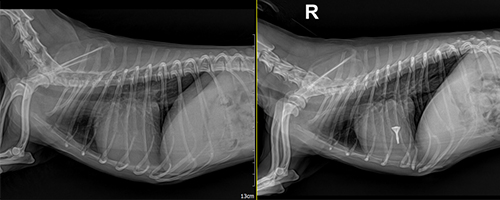

수술 전/후 방사선

수술 전/후 방사선 이미지

이미지 준비 중